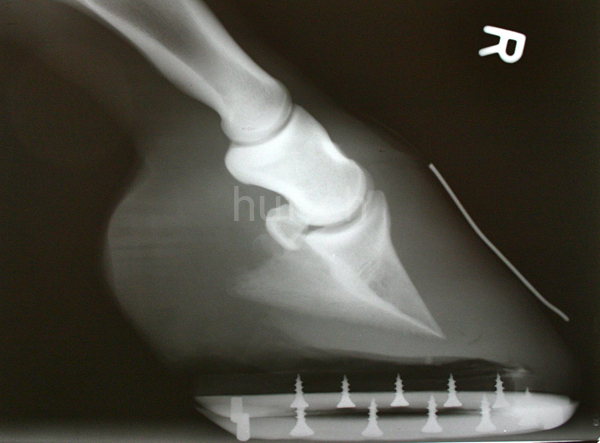

Korrekturen der Hufe müssen sehr überlegt angewendet werden, da die Entscheidung für oder gegen eine Korrektur weitreichende Folgen hat. Wendet man Stellungskorrekturen aufgrund falscher Rückschlüsse aus der Stellungsbeurteilung an, kann das massive Schäden zur Folge haben. So können Korrekturen Arthrosen oder Bänderzerrungen begünstigen, die ohne die Fehleinschätzung gar nicht entstanden wären.

Sowohl bei der Beurteilung als auch bei den Korrekturen der Hufe, gibt es markante Unterschiede zwischen den Hufen der Vorder- und denen der Hintergliedmaßen, da beide unterschiedliche Aufgaben besitzen. Während die Vorderhand den schweren Teil des Rumpfes trägt, erzeugt die Hinterhand den Schub für die Vorwärtsbewegung und trägt den leichteren Teil des Rumpfs. Deshalb sind die Vorder- und Hinterhufe unterschiedlich geformt. Die runde Form des Vorderhufs kommt der Stützaufgabe durch die breitere Fläche entgegen. Die schmaleren, langovalen Hinterhufe dagegen können den durch den Schub entstehenden Kräften besser widerstehen. Den Hinterhuf beispielsweise in eine runde Form zu korrigieren, wäre also völlig kontraproduktiv.